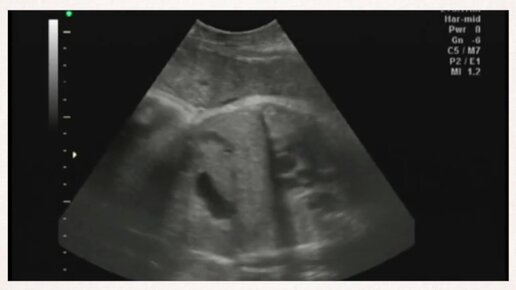

УЗИ на 37 неделе беременности